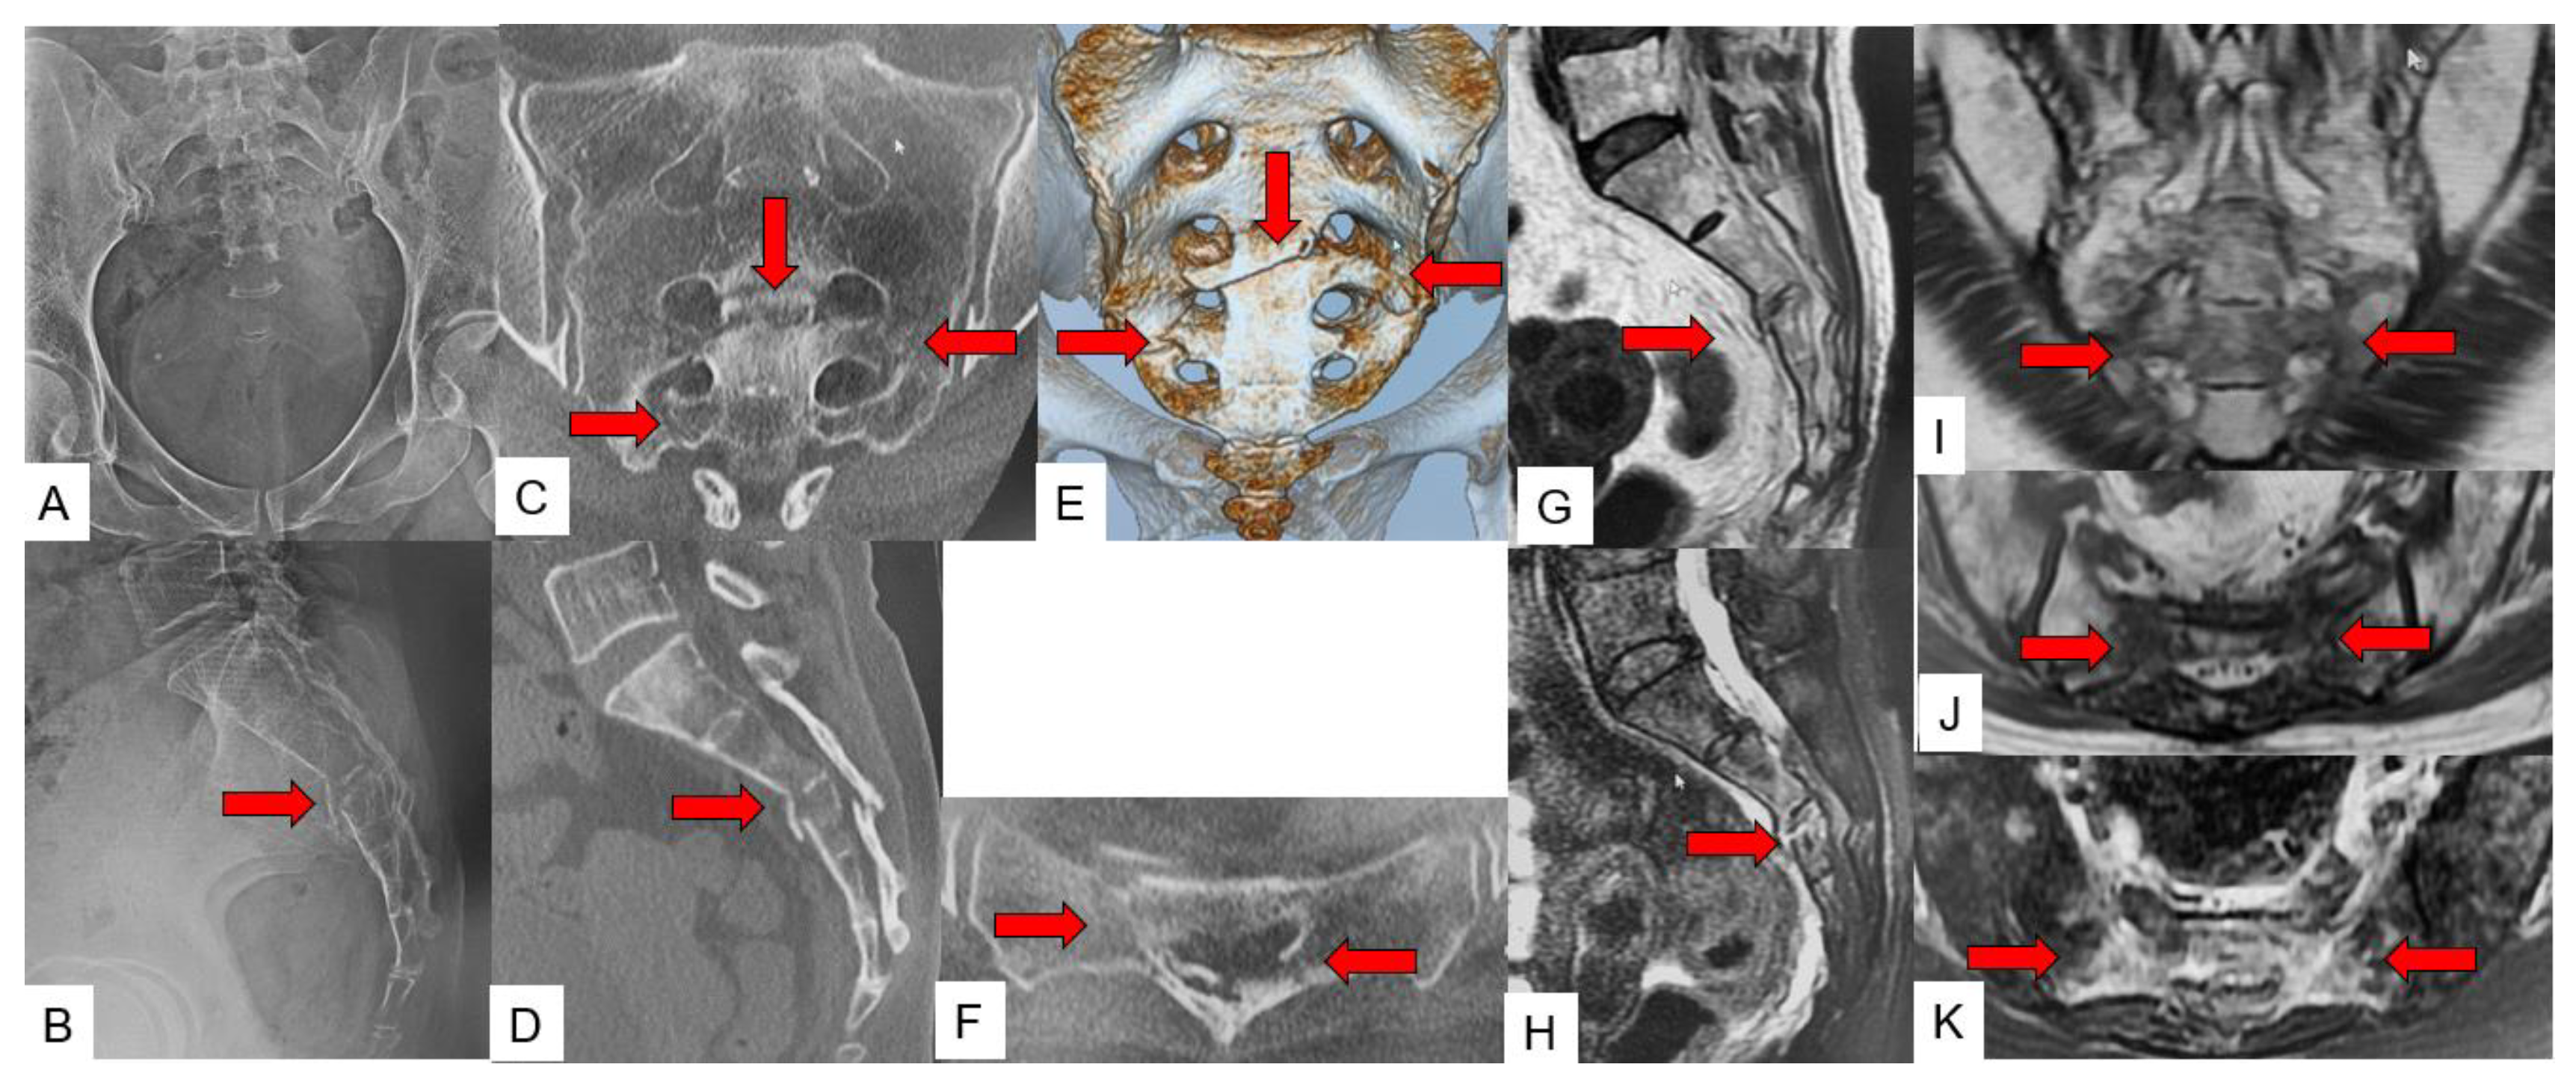

3.2. Accompanying Other Fracture

3.3. SIF Fracture Pattern

3.4. Typical SIF Case